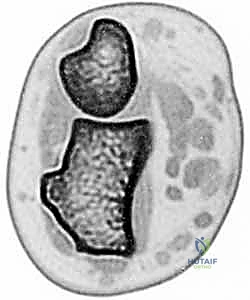

* CT Scans: These are invaluable, especially for assessing bony morphology and subtle subluxation.

* Crucially, CT must be performed on both wrists, with images obtained in identical forearm rotation (typically neutral) for direct comparison. This allows us to quantify translation and identify incongruity.

* Consider adding stress views during imaging to unmask subtle instability.